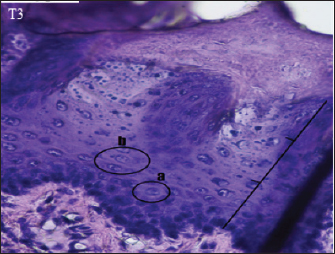

Fig. 3. Histopathological description of the rat tongue epithelium in the T1 group, microscope at ×400. (a) the ratio between the nucleus and the cytoplasm increases, with a hyperchromatic nucleus; (b) the shape of the nucleus showing anisonucleus.

The histopathology of the tongue epithelium of rats in the T1 group revealed dysplastic cells. Cell form and size variations (anisocytosis and pleomorphism) and irregular epithelial stratification due to nuclear shape and size differences. The ratio of nuclei to cytoplasm rises, and hyperchromatic nuclei are visible. Cell changes affect two-thirds of the thickness of the rat tongue epithelium. Therefore, this is classified as mild dysplasia (Fig. 3).

The T1 group had dysplastic alterations in the epithelium of the rat tongue as the (C+) group. This group exhibited mild dysplasia limited to one-third of the epithelium (basal and parabasal layers). According to Speight (2007), moderate dysplasia (grade II) is characterized by abnormal cell proliferation extending to the middle third of the epithelium, more severe cytological alterations than mild dysplasia, and the presence of hyperchromatic cells and prominent nuclei. Loss of basal polarity can be observed near the base of the epithelium, indicating tissue alterations.